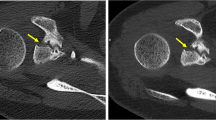

Region-of-interest (ROI) measurements were performed to objectify the effectiveness of PC-CT130 keV for metal artifact reduction compared to the PC-CTstd reconstruction. For this purpose, a 10-mm2 circular ROI was placed in the area with the subjectively most severe artifact appearance caused by photon starvation in PC-CTstd. ROI size and location were kept similar for the corresponding measurements in the PC-CTstd reconstruction. In addition, a second ROI (10 mm2) was placed in a distant muscle as far away as possible from the implant and in an area subjectly not affected by the artifact serving as reference. An image example is given in Fig. 2(A/B). The mean Hounsfield unit (HU) values from these ROIs were read for PC-CTstd and PC-CT130 keV.

A and B Example for quantitative assessment of artifacts/artifact reduction in an area with subjectively the most severe artifact appearance (green ROI) and in a distant muscle (red ROI) not affected by the artifact serving as reference in (A) PC-CTstd and in (B) PC-CT130 keV reconstructions. C and D Mean HU values from the ROIs of all patients were compared between PC-CTstd and PC-CT130 keV in the artifact as well as in distant muscle. PC-CTstd = photon-counting CT; PT-CT130 keV = PC-CT with monoenergetic reconstructions at 130 keV; HU = Hounsfield unit

Quantitative measurements revealed a significant artifact reduction for PC-CT130 keV compared to PC-CTstd. Mean HU values of the ROI within the subjectively most severe artifact were significantly lower in the PC-CTstd vs. the PC-CT130 keV reconstruction (− 462 ± 191 HU vs. 26 ± 108 HU, respectively; p < 0.001). No significant differences were found in the measurements of the reference ROI placed in the distant muscle subjectively not affected by the artifact (48 ± 19 HU vs. 46 ± 15 HU; p = 0.575; Fig. 2).